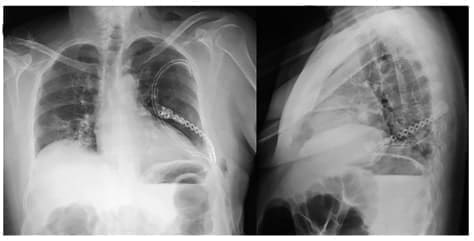

Mediante una incisión en piel sobre el séptimo arco costal, se identificó una lesión de aproximadamente 1,5 cm, que abombaba la cortical, sin infiltración de los tejidos adyacentes. Se resecó la lesión y el séptimo arco costal, preservando un margen anterior y posterior de 3 cm, para posteriormente reconstruir la pared torácica con una barra de titanio y una malla de polipropileno, para evitar el riesgo de herniación pulmonar.

Se verificó la adecuada expansión pulmonar y se realizó el cierre muscular por planos. No hubo complicaciones y el posoperatorio transcurrió de forma adecuada. Las radiografías de tórax de control no mostraron hallazgos patológicos ni recidiva de la enfermedad (figura 2).

Figura 2. Radiografía anteroposterior y lateral de tórax al primer día postoperatorio